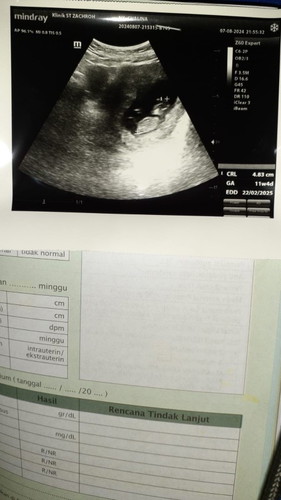

Alhamdulillah hasil usg semua nya sehat dan janin nya aktif kata dokter nyaa dan udh ada detak jantungnya tp msh lompat2tan kata dokternyaa hehe air ketuban juga cukup dan baguss..sblmnyaa hpl ku d apk ini maret bund dan usia kandunganku d apk ini 10w3d tp ternyata hasil usg hpl ku febuari dan usia kehamilan skrg 11w4d,emg bsa beda gtu ya bund??#Sharing_dong_Bund